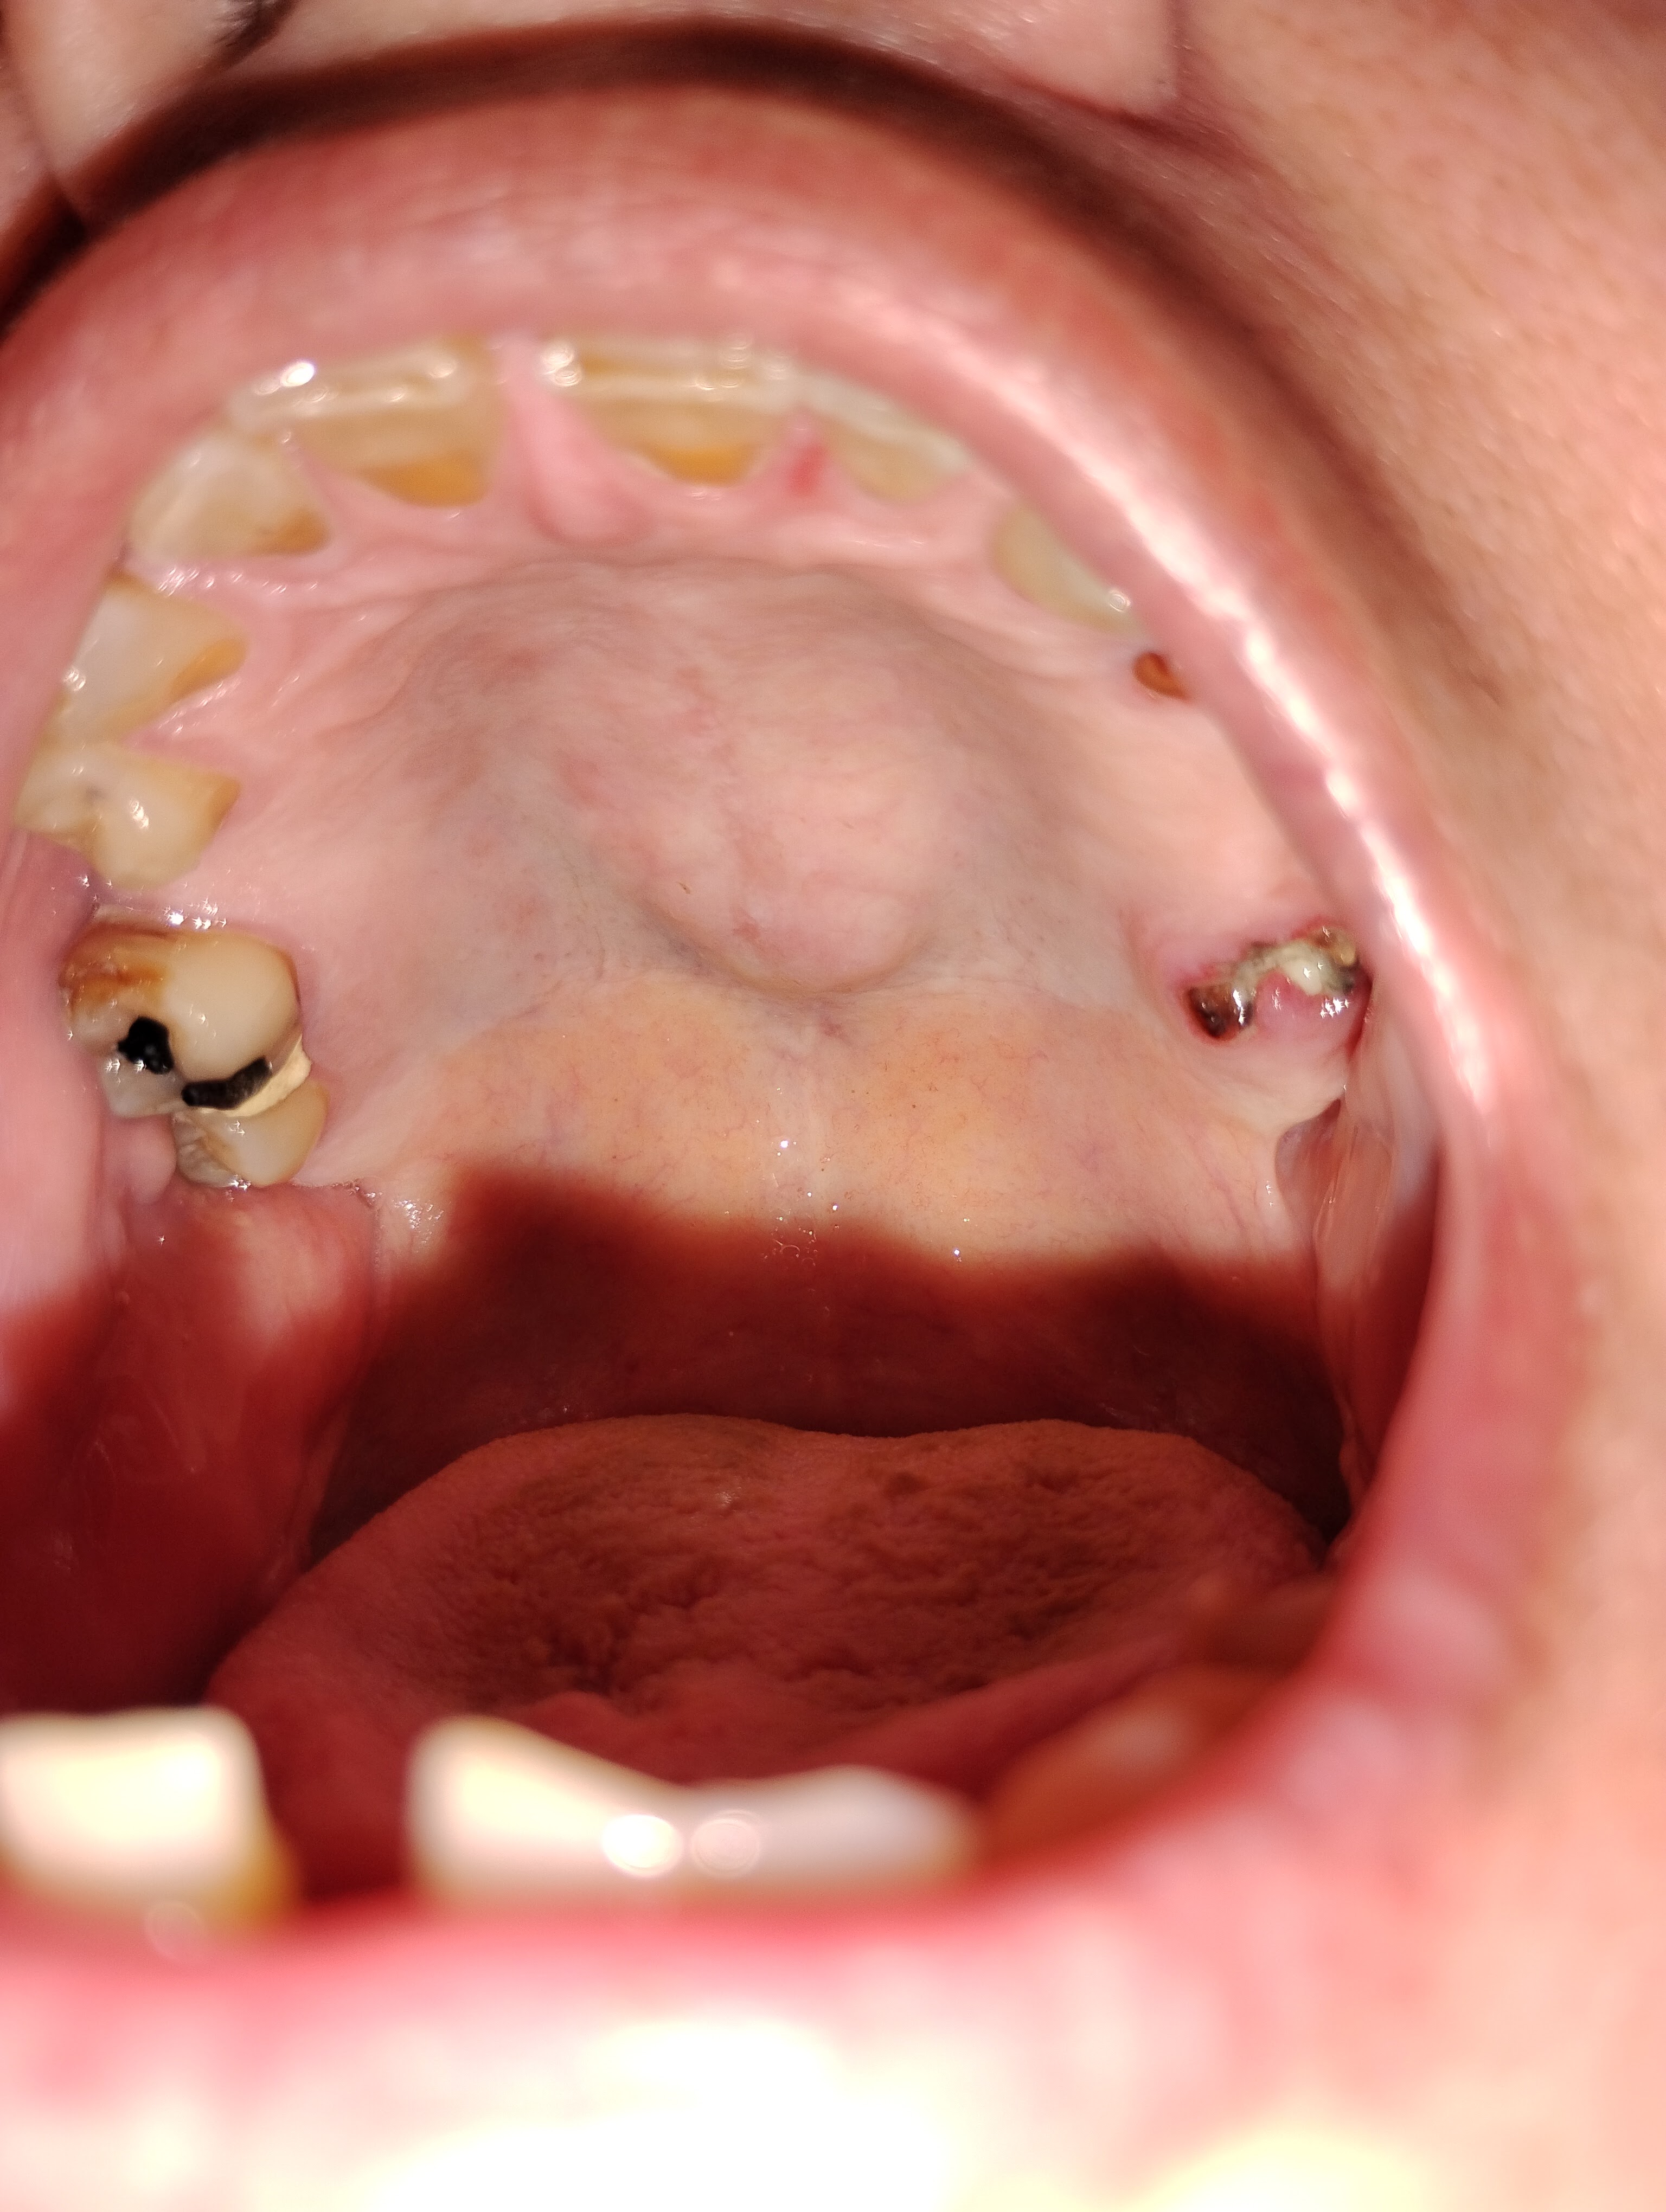

> I’m also facing advanced dental disease, with gum infections and tooth loss that affect my health, speech, and confidence. We both need urgent care—not just to survive, but to live with dignity.

> - Dena’s dental surgeries and periodontal care